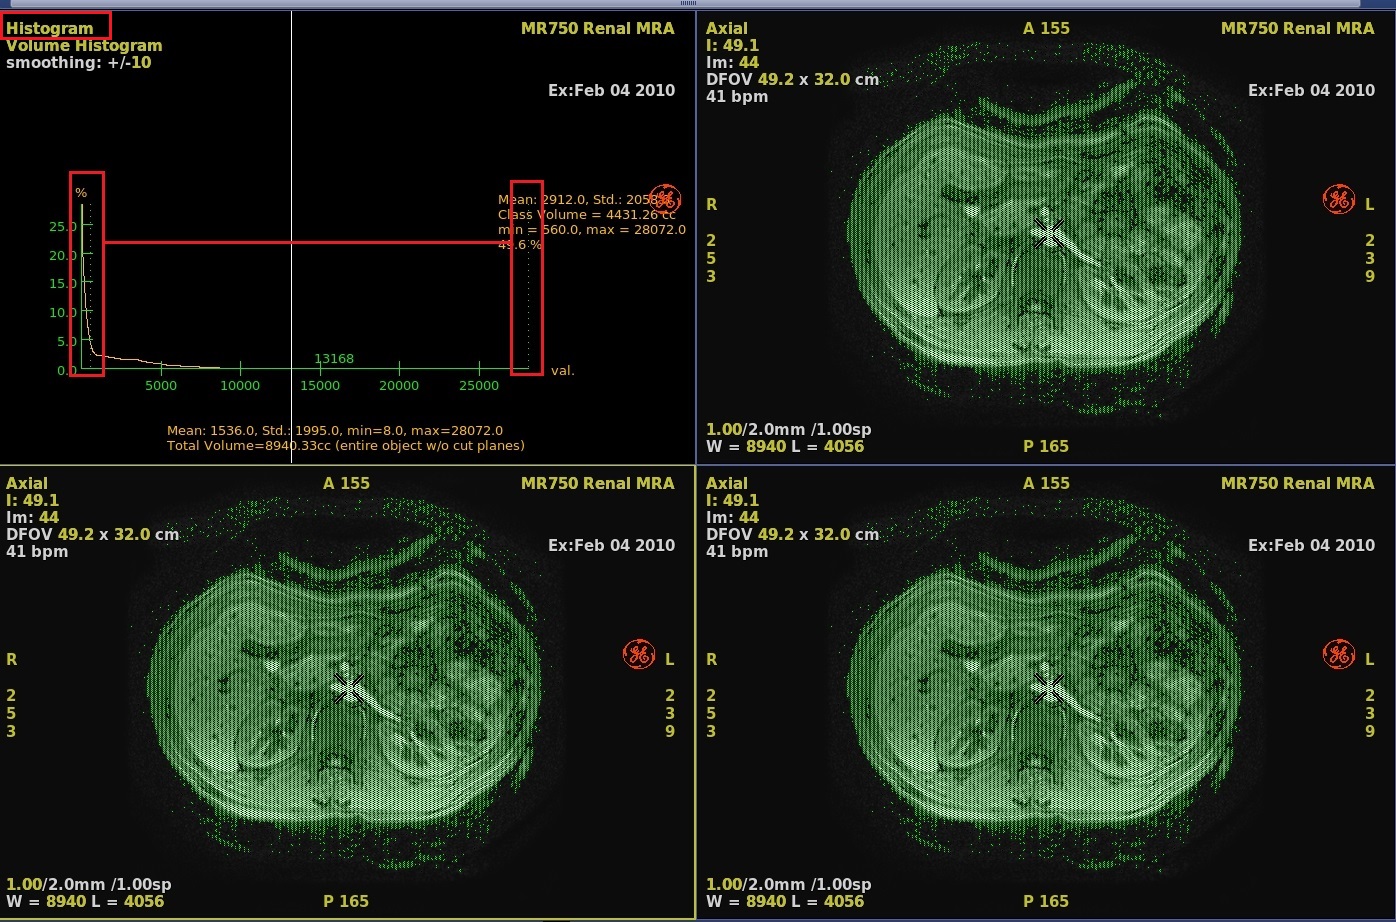

Figure 1. Example of Click and drag threshold dashed lines to encompass anatomy of interest

- On the histogram graph, click and drag the green dashed line to adjust the threshold.

2. Voxel reference line Move the voxel reference line to select a class of voxels. 3. Voxel class statistics A voxel class refers to a range (class) of voxels whose values are specific to a certain anatomical feature (e.g. bone surrounded by muscle, or a tumor surrounded by healthy tissue). 4. Class boundaries

Class boundary lines located on both sides of the center white line, mark the upper and lower limit of a class (range) of voxel values around the voxel reference line whose values are specific to a certain anatomical feature (e.g. bone surrounded by muscle, or a tumor surrounded by healthy tissue). These boundaries are calculated automatically and displayed as green thin dotted lines. You can move them manually to delimit an exact range of voxel values. The software analyzes the peaks and valleys of the histogram curve and determines the voxel class around the current voxel reference line from the changes in slope (the inflection points) of the histogram curve. Set the smoothing value as required before using the class boundaries.

5. Statistics Statistics about the voxel values (mean, standard deviation, maximum, and minimum) within the class defined by the boundary lines, and the computed value of the corresponding surface area or volume.